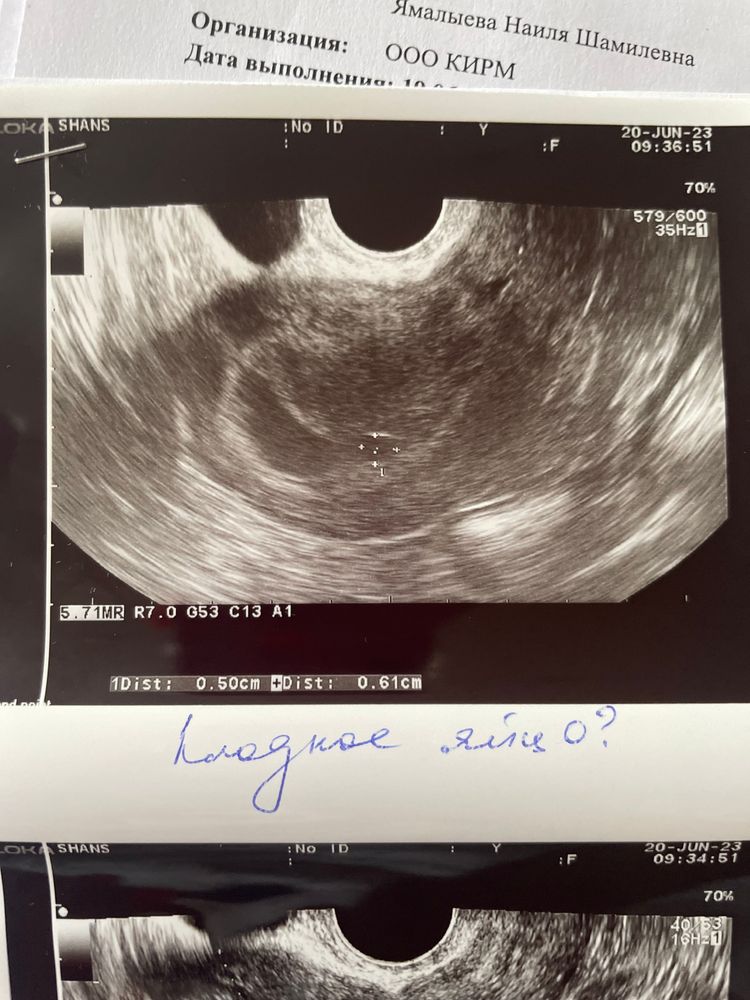

Повторное узи при пустом плодном яйце

То ли фото не очень качественные, то ли.. на первых двух снимках мне больше видятся сгустки крови. На третьем действительно похоже на плодное яйцо (но и гематомы бывают такой формы). На 28 ДПП как минимум должны были увидеть желточный мешок в плодном яйце. А так обычно эмбрион с СБ+. Можно еще несколько дней подождать и переделать УЗИ, лучше прям хорошего узиста и аппарат найти.

Виктория, хгч результат 16947

История ЭКО. 6н3д. Как определяют соответствующий срок УЗИ?